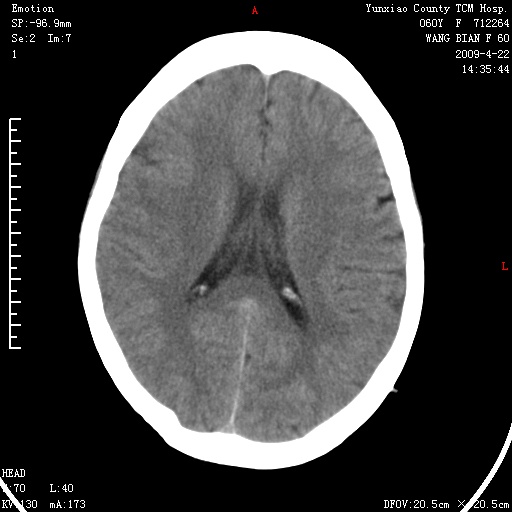

1、头颅未见明显异常。

1、枕骨蛛网膜粒压迹。2、左肾囊肿可能。建议增强

1)枕骨蛛网膜粒压迹。2)左肾囊肿可能。